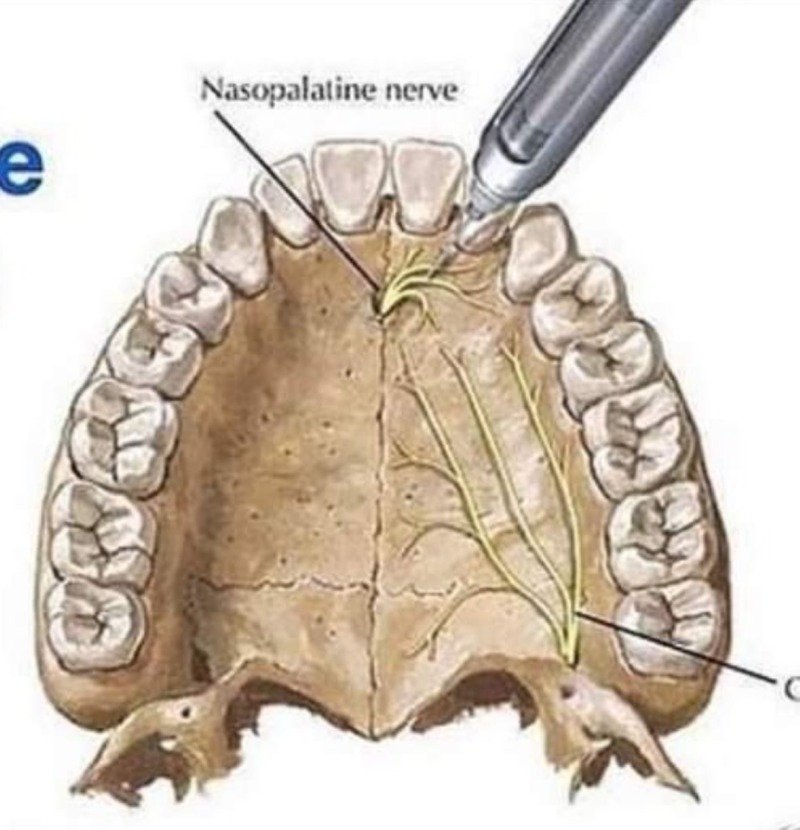

(+ 단단할 입천장은 마취약이 퍼지는 범위도 좁아서 필요하면 여러 번 찔러야 한다고)